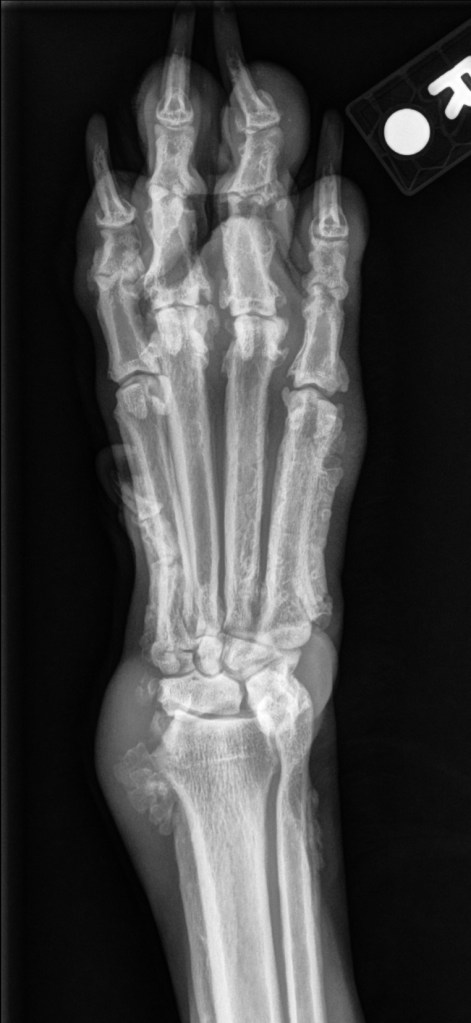

9yr FS Large Mixed Breed Dog. Swollen carpi and paws with progressive lameness.